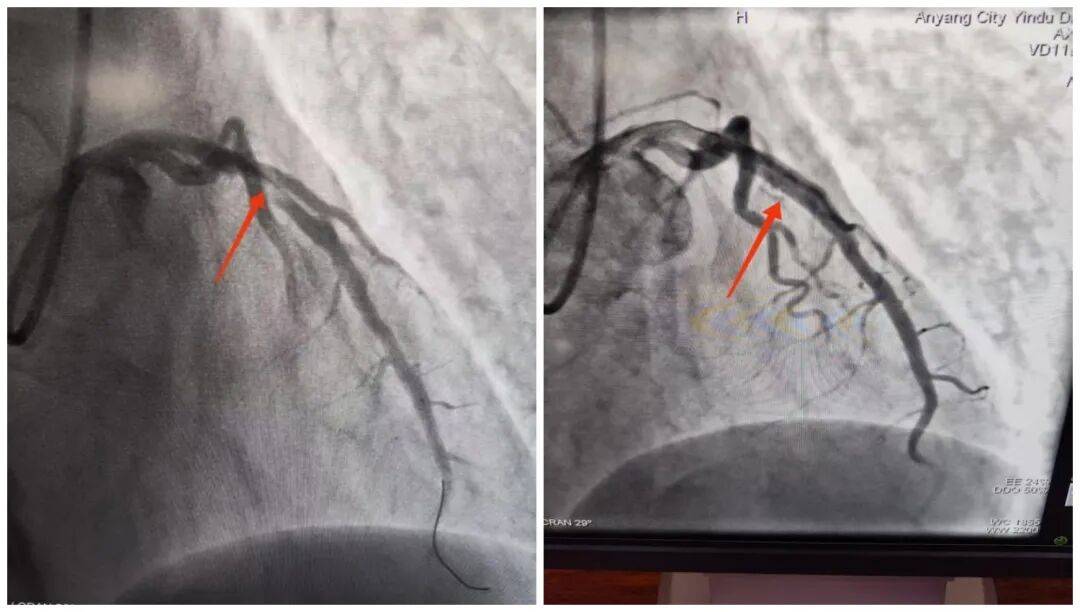

14:54,承載著生命希望的救護(hù)車抵達(dá)殷都區(qū)人民醫(yī)院大門口。14:56,劉大爺被推至導(dǎo)管室門口,早已等候在此的醫(yī)護(hù)團(tuán)隊(duì)立即上前,無縫銜接將劉大爺推進(jìn)導(dǎo)管室,手術(shù)隨即開始。15:18,醫(yī)院介入團(tuán)隊(duì)精準(zhǔn)操作,治療導(dǎo)絲成功通過病變部位,血管開通的關(guān)鍵一步順利完成。15:50,手術(shù)圓滿結(jié)束,成功挽救了瀕臨壞死的心肌。從劉大爺?shù)竭_(dá)殷都區(qū)人民醫(yī)院門口到成功開通堵塞血管,整個(gè)過程僅用了24分鐘,這一速度遠(yuǎn)優(yōu)于國際通行的90分鐘黃金標(biāo)準(zhǔn)。

此次對(duì)劉大爺?shù)某晒戎?,并非偶然,而是“心電一張網(wǎng)”打破診療壁壘、實(shí)現(xiàn)雙院高效聯(lián)動(dòng)的生動(dòng)實(shí)踐。曲溝衛(wèi)生院作為基層網(wǎng)絡(luò)醫(yī)院,在救治初期快速完成基礎(chǔ)檢查與初步處置,為后續(xù)治療“打底”;殷都區(qū)人民醫(yī)院專業(yè)團(tuán)隊(duì)則憑借精湛技術(shù)和高效協(xié)作,精準(zhǔn)“接力”,確保救治方案快速落地、手術(shù)順利推進(jìn)。兩者緊密配合,真正打通了轄區(qū)內(nèi)急性胸痛患者的分級(jí)救治綠色通道,為群眾的生命健康筑起了一道堅(jiān)實(shí)的“防護(hù)墻”。